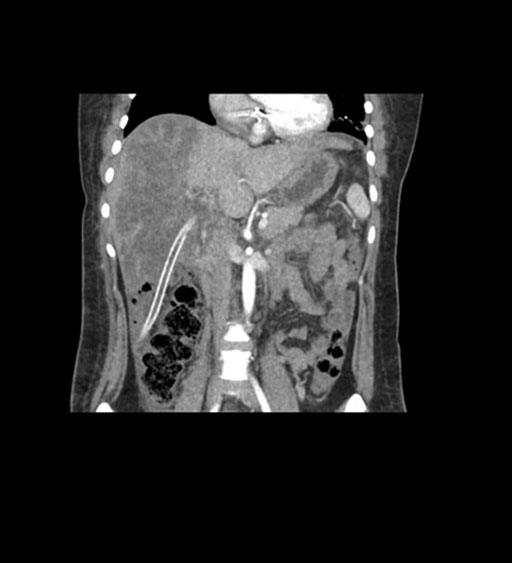

Coronal Venous